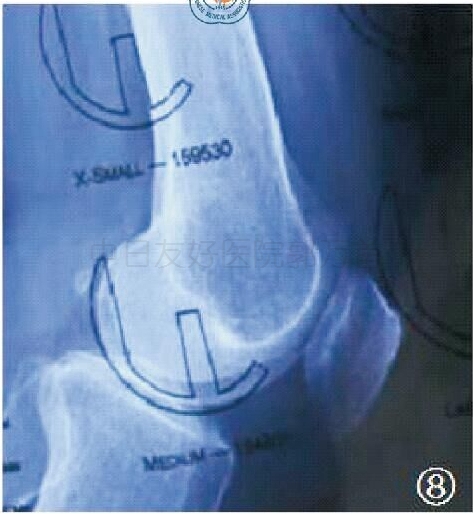

X线片五:术前模板测量

术前使用X线模板来选择股骨假体的型号,将模板的轮廓紧贴X线片的股骨内侧髁,股骨假体的中央栓应与股骨干的长轴平行。不论是股骨髁远端还是股骨后髁,模板轮廓的外表面均应超出X线大约2 mm,以保证关节软骨的厚度。